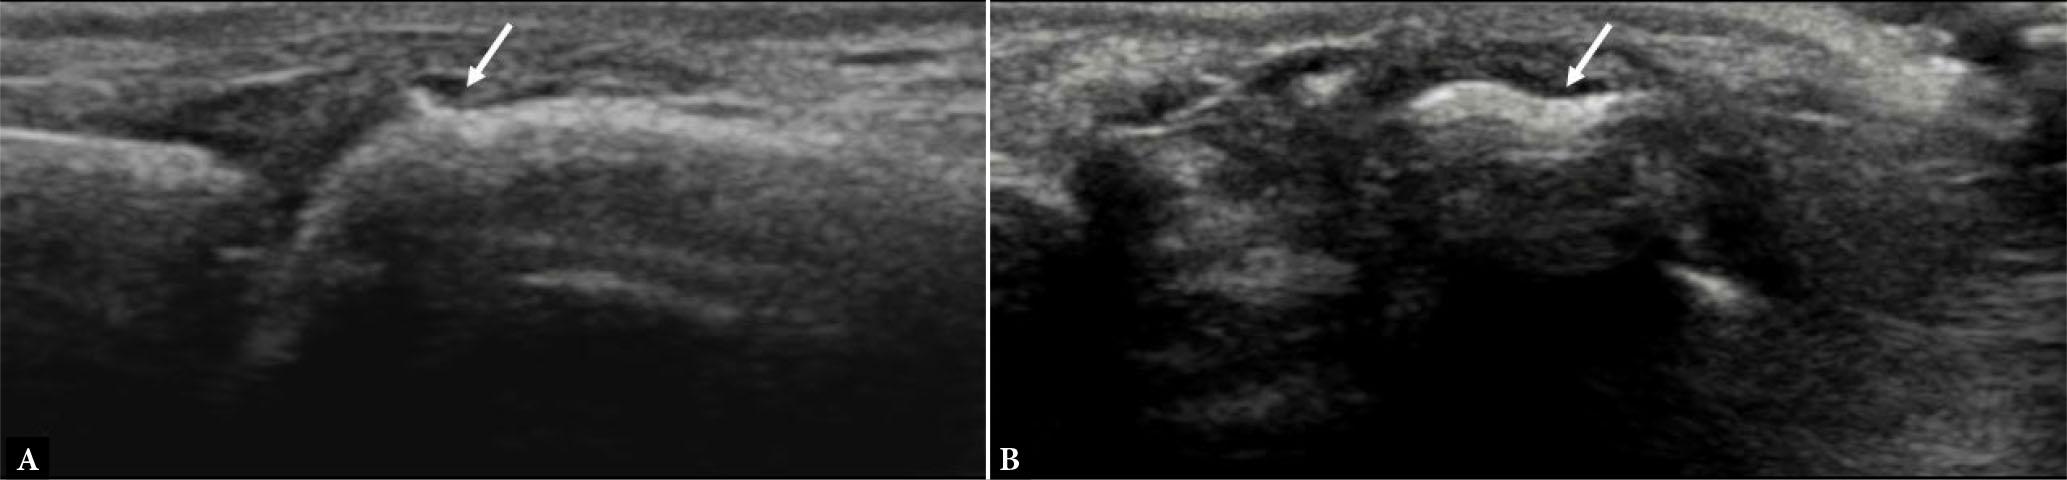

On HRUS, enthesitis appears as heterogeneous hypoechogenicity of the enthesis, loss of normal fibrillar echotexture of the tendon insertion, intratendinous hypoechoic areas, punctate calcific foci, blurring of tendon margins, thickening of the insertion site of tendon, irregularities, and erosions of subentheseal bone, and perientheseal swelling (Fig. 15). Perientheseal diffusion of inflammatory fluid noted on imaging has been reported to be a characteristic finding of SpA and cause perientheseal swelling(22). Multiple and irregular enthesophytes and calcific deposits are more specific for SpA-related enthesitis(22). PDUS can show an increased signal in active inflammation of the enthesis and can be used to assess treatment response (Fig. 16).

Enthesitis. Long-axis US images of Achilles tendon show loss of normal fibrillar echotexture and decreased echogenicity of the tendon insertion (asterisks), punctate calcific foci (small arrow in B), erosions of subentheseal bone (large arrows in A and B) and power Doppler signal at enthesis as seen in B

Enthesitis. Short-axis grayscale (A) and power Doppler (B) US images of tibialis posterior tendon (asterisks) show intra-tendinous and peritendinous thickening and power Doppler signal